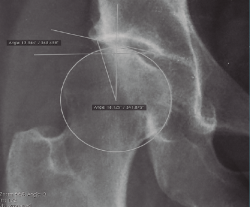

- El grupo de Berna(11)y el de la Mayo Clinic han descrito signos radiológicos cuya sola presencia aumenta la probabilidad de mal resultados en comparación con la ausencia de los mismos: a) osteofito en la fosa (multiplica por 3,2 veces la posibilidad de mal resultado); b) geodas subcondrales > 5 mm (multiplica por 4,1); y c) lesiones condrales de grado 3-4 que afecten al menos a 60° de la circunferencia acetabular (multiplica por 4,6). Además, los pacientes de CFA intervenidos con el hallazgo preoperatorio de estos 3 signos asocian un 0% de supervivencia a 6 años y los que tienen el a) y el c) un 20% a 6 años. De ahí que debamos buscar la presencia de estos y otros signos descritos en el artículo para informar a nuestro paciente de las posibilidades de éxito (Figura 1).

Figura 1. Paciente de 44 años con espacios < 2 mm en la zona 3, geodas subcondrales y osteofito de fosa. Pese a los factores en su contra, sus expectativas razonables nos inclinaron por la cirugía artroscópica. En la imagen de la derecha, resección del osteofito de fosa.